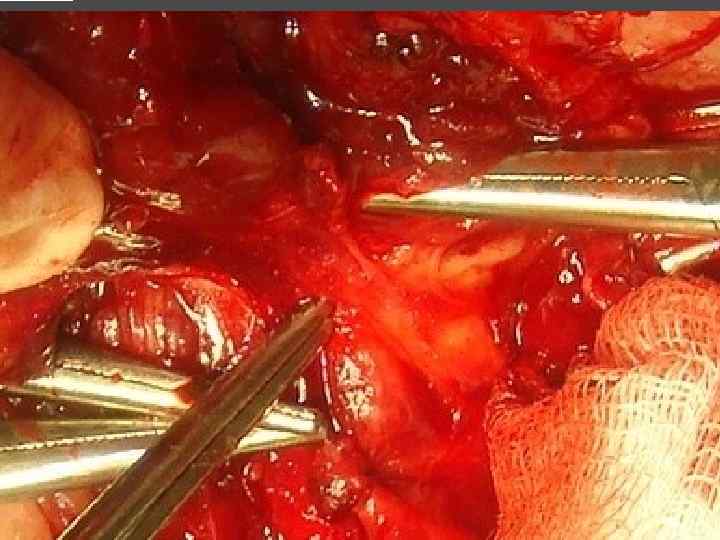

ХИРУРГИЧЕСКОЕ ЛЕЧЕНИЕ ЗОБА

ХИРУРГИЧЕСКОЕ ЛЕЧЕНИЕ ЗОБА

ОСЛОЖНЕНИЯ ХИРУРГИЧЕСКОГО ЛЕЧЕНИЯ ►Поражение возвратного нерва, приводящее к параличу голосовой связки на стороне поражения, как следствие – изменение тембра голоса, сужение голосовой щели, затруднение дыхания. ► Кровотечение. ►Тиреотоксический криз. ► Гипопаратиреоз. ► Рецидив тиреотоксикоза. ► Формирование порочного рубца.

ЛЕЧЕНИЕ Консервативное – возможно только у больных вторичным гиперпаратиреозом, при уровне паратгормона не превышающим 800 пг/мл. Хирургическое – паратиреодэктомия.

ЭКТОПИРОВАННАЯ В ТИМУС ПАРАЩИТОВИДНАЯ ЖЕЛЕЗА